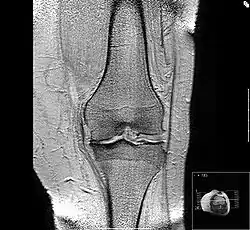

MRI of osteoarthritis in the knee, with characteristic narrowing of the joint space -

Primary osteoarthritis of the left knee. Note the osteophytes, narrowing of the joint space (arrow), and increased subchondral bone density (arrow). -